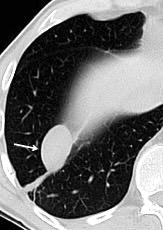

En el hemotórax, los elementos formes de la sangre tienden a depositarse en la parte más declive

Polireddy K et al. Blunt thoracic trauma: role of chest radiography and comparison with CT findings and literature review . Emerg Radiol 2022.

Neumo-Hemotórax

Sin fracturas: 6,7%

1-2 fracturas: 24,9% + de 3 fracturas:81,4%

Colección pleural

Hemorrágica.30-70 UH

Extravasación iv con sangrado activo.>90 UH “Simpático”..<15 UH